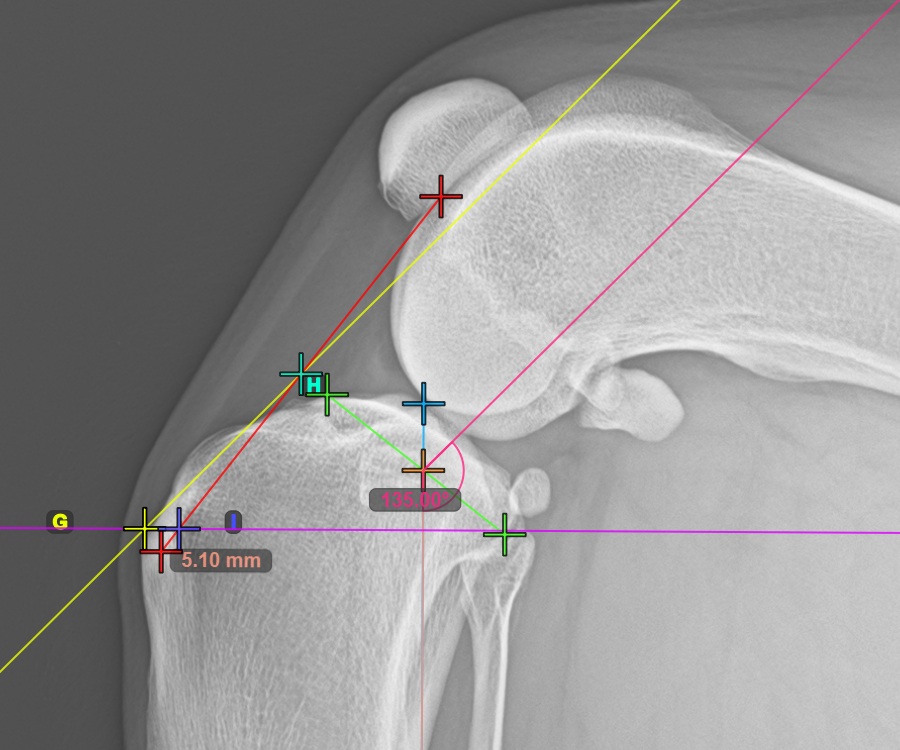

To complete the TTA Rapid variant of TTA measurement procedure mark the most dorsal point of the Crista Tibiae (Tuberositas Tibiae). The distance between the Tuberositas Tibiae and the automatic TTA Rapid helper lines is the required adjustment for the TTA procedure.

The image below depicts the usual placement of the tibial tuberosity, the most prominent point of the tibial crest.

Modify the points constructing the measurement to recalculate the required advancement that should be made during the TTA procedure.